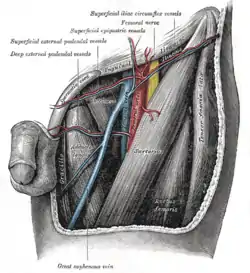

The left femoral triangle. (Superficial external pudendal vessels labeled at upper left.) | |

The great saphenous vein and its tributaries at the fossa ovalis.

The great saphenous vein and its tributaries at the fossa ovalis. The femoral vein and its tributaries.